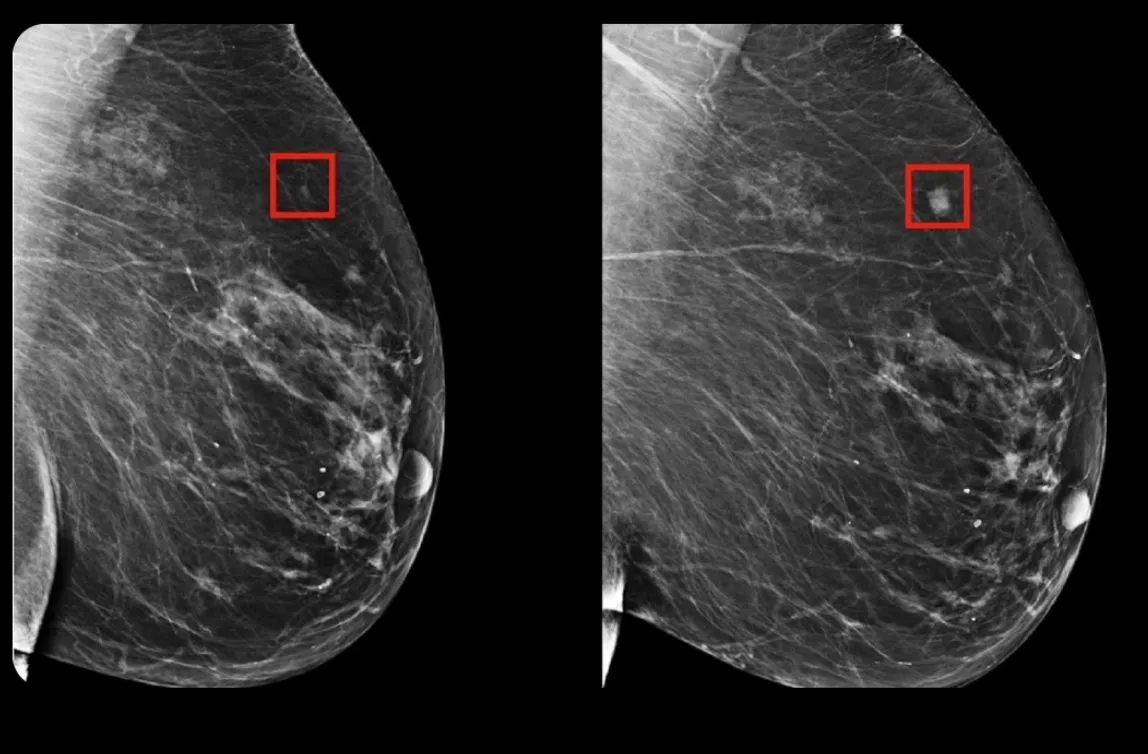

C'est vrai, mais ce n'est pas nouveau. Le modèle d'IA nommé MIRAI est capable de détecter les futurs cancers du sein. Ce modèle est développé depuis 2019 grâce à une collaboration entre le MIT et la clinique Jameel. En 2021, ils ont amélioré leur modèle et effectué des tests à grande échelle, notamment en Suède et à Taïwan. Un article scientifique a été publié dans la revue Science en janvier 2021. 🌐 https://news.mit.edu/2019/using-ai-predict-breast-cancer-and-personalize-care-0507 🌐 https://news.mit.edu/2021/robust-artificial-intelligence-tools-predict-future-cancer-0128 🌐 https://www.science.org/doi/10.1126/scitranslmed.aba4373 Il est intéressant de noter que MIRAI est encore en test de manière prospective et rétrospective dans plusieurs pays. Cela permet de s'assurer que le modèle fonctionne correctement avant qu'il puisse être déployé dans les hôpitaux. 🌐 https://jclinic.mit.edu/mirai-faq/ D'ailleurs, c'est intriguant de voir que ce modèle d'IA, qui date de trois ans (ce qui est une éternité dans le monde académique), est republié en masse sur les réseaux sociaux. Nous n'avons pas trouvé la source originelle qui a commencé cette tendance. Serait-ce le début d'un soulèvement de l'IA? 🤖